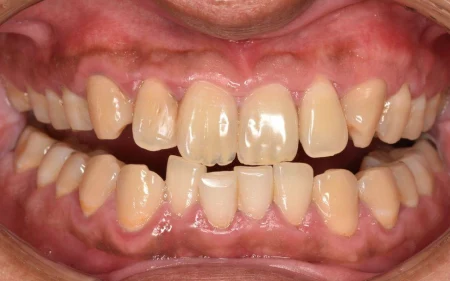

一般歯科 2023.0450代男性「着色を落として、詰め物もやり直したい」歯周病治療と専用機械による着色除去を並行し、歯と歯肉の状態を改善して詰め物をやり直す準備ができた症例